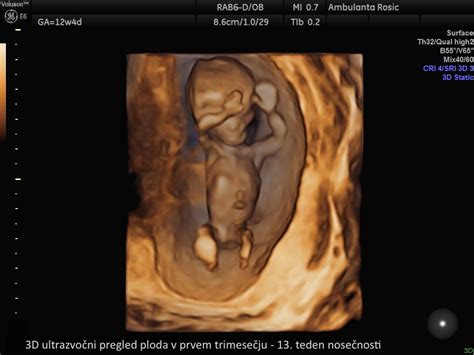

- 3D/4D ultrazvok: Omogoča prikaz ploda v tridimenzionalni obliki in gibanju, kar lahko staršem prinese nepozaben vpogled v razvoj svojega otroka. Cene 3D/4D ultrazvoka se gibljejo med 80 € in 120 €.